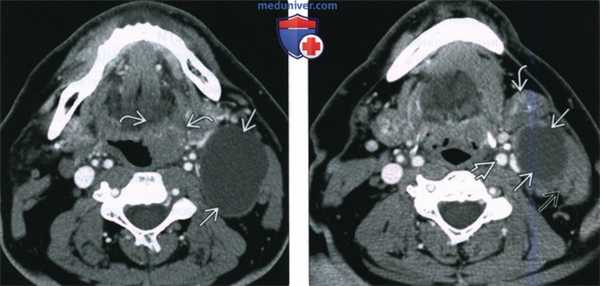

(Слева) При аксиальной КТ с КУ не определяется патологических изменений со стороны корня языка с обеих сторон, лимфатические узлы уровня IIА не увеличены.

(Справа) При аксиальной КТ у этого же пациента в правой половине шеи визуализируется кистозное образование с перегородкой. Была выполнена тонкоигольная аспирация этого образования, подтвердился плоскоклеточный рак. При эндоскопической биопсии корня языка справа обнаружился ВПЧ(+) ПКР. Небольшие первичные опухоли корня языка могут быть незаметны при томографии. Характерной особенностью ВПЧ(+) ПКР является наличие вторично измененных увеличенных лимфатических узлов, выглядящих кистозными, в то время как первичная опухоль имеет небольшой размер. (Слева) При аксиальной КТ с КУ у пациента с жалобами на боль в правом ухе и выраженным увеличением шейных лимфоузлов, в правой небной миндалине В визуализируется небольшое образование, накапливающее контраст. При отсутствии лимфаденопатии это можно было бы считать вариантом нормы.

(Справа) При аксиальной КТ с КУ у этого же пациента в передних отделах справа визуализируется увеличенный лимфоузел уровня IIА В с участками некроза (включения низкой плотности). При гибридизации in situ подтвердилась вирусная инфекция (ВПЧ-16). Первичная опухоль обычно расположена в ротоглотке в корне языка или в небной миндалине на стороне вторично измененного лимфоузла.